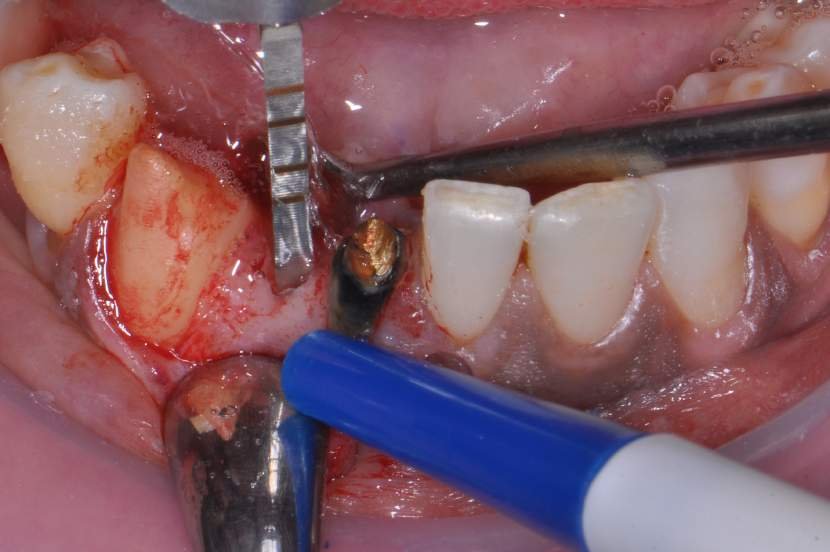

TÉCNICA CIRÚRGICA

O procedimento cirúrgico para os implantes Slim segue um protocolo semelhante como outros implantes, porém muito simplificado. Normalmente utilizase a técnica anestésica infiltrativa. Um retalho mucoperiosteal deve ser rebatido para uma observação direta do rebordo ósseo disponível. No entanto, quando o tecido queratinizado e o volume ósseo abundantes estiverem presentes, uma cirurgia flapless é muitas vezes o protocolo cirúrgico de escolha.2

Para instalação de implantes de Ø 2.5mm é necessário apenas a utilização da fresa lança diâmetro de 2.0 mm. E para instalação de implantes de 3.0 mm utilização da fresa lança diâmetro de 2.0 mm e opcionalmente a fresa Countersink Slim 3.0mm (em casos de osso tipo I ou tipo II). O implante tem o ápice cortante e espiras que facilitam sua instalação. Os implantes Slim se apresentam de 1 em 1 mm de comprimento de 7 a 13 mm, o que facilita muito a escolha dos tamanhos no momento do planejamento.

CASO CLÍNICO

Paciente com perda do incisivo central inferior do lado direito, utilizando uma prótese fixa em zircônia com estética e adaptação deficientes.